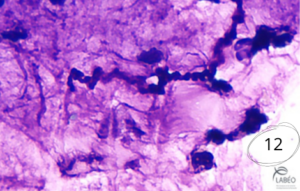

Spirales de mucus (Spirales de Curschmann) - photo 10

• Accumulation de mucus dans les bronches/bronchioles.

• Témoignent d’une altération de la production de mucine en contexte inflammatoire.

• Fréquentes dans l’asthme équin sévère, mais possibles dans d’autres affections (ex. fibrose pulmonaire multinodulaire équine) – LBA indispensable pour confirmation